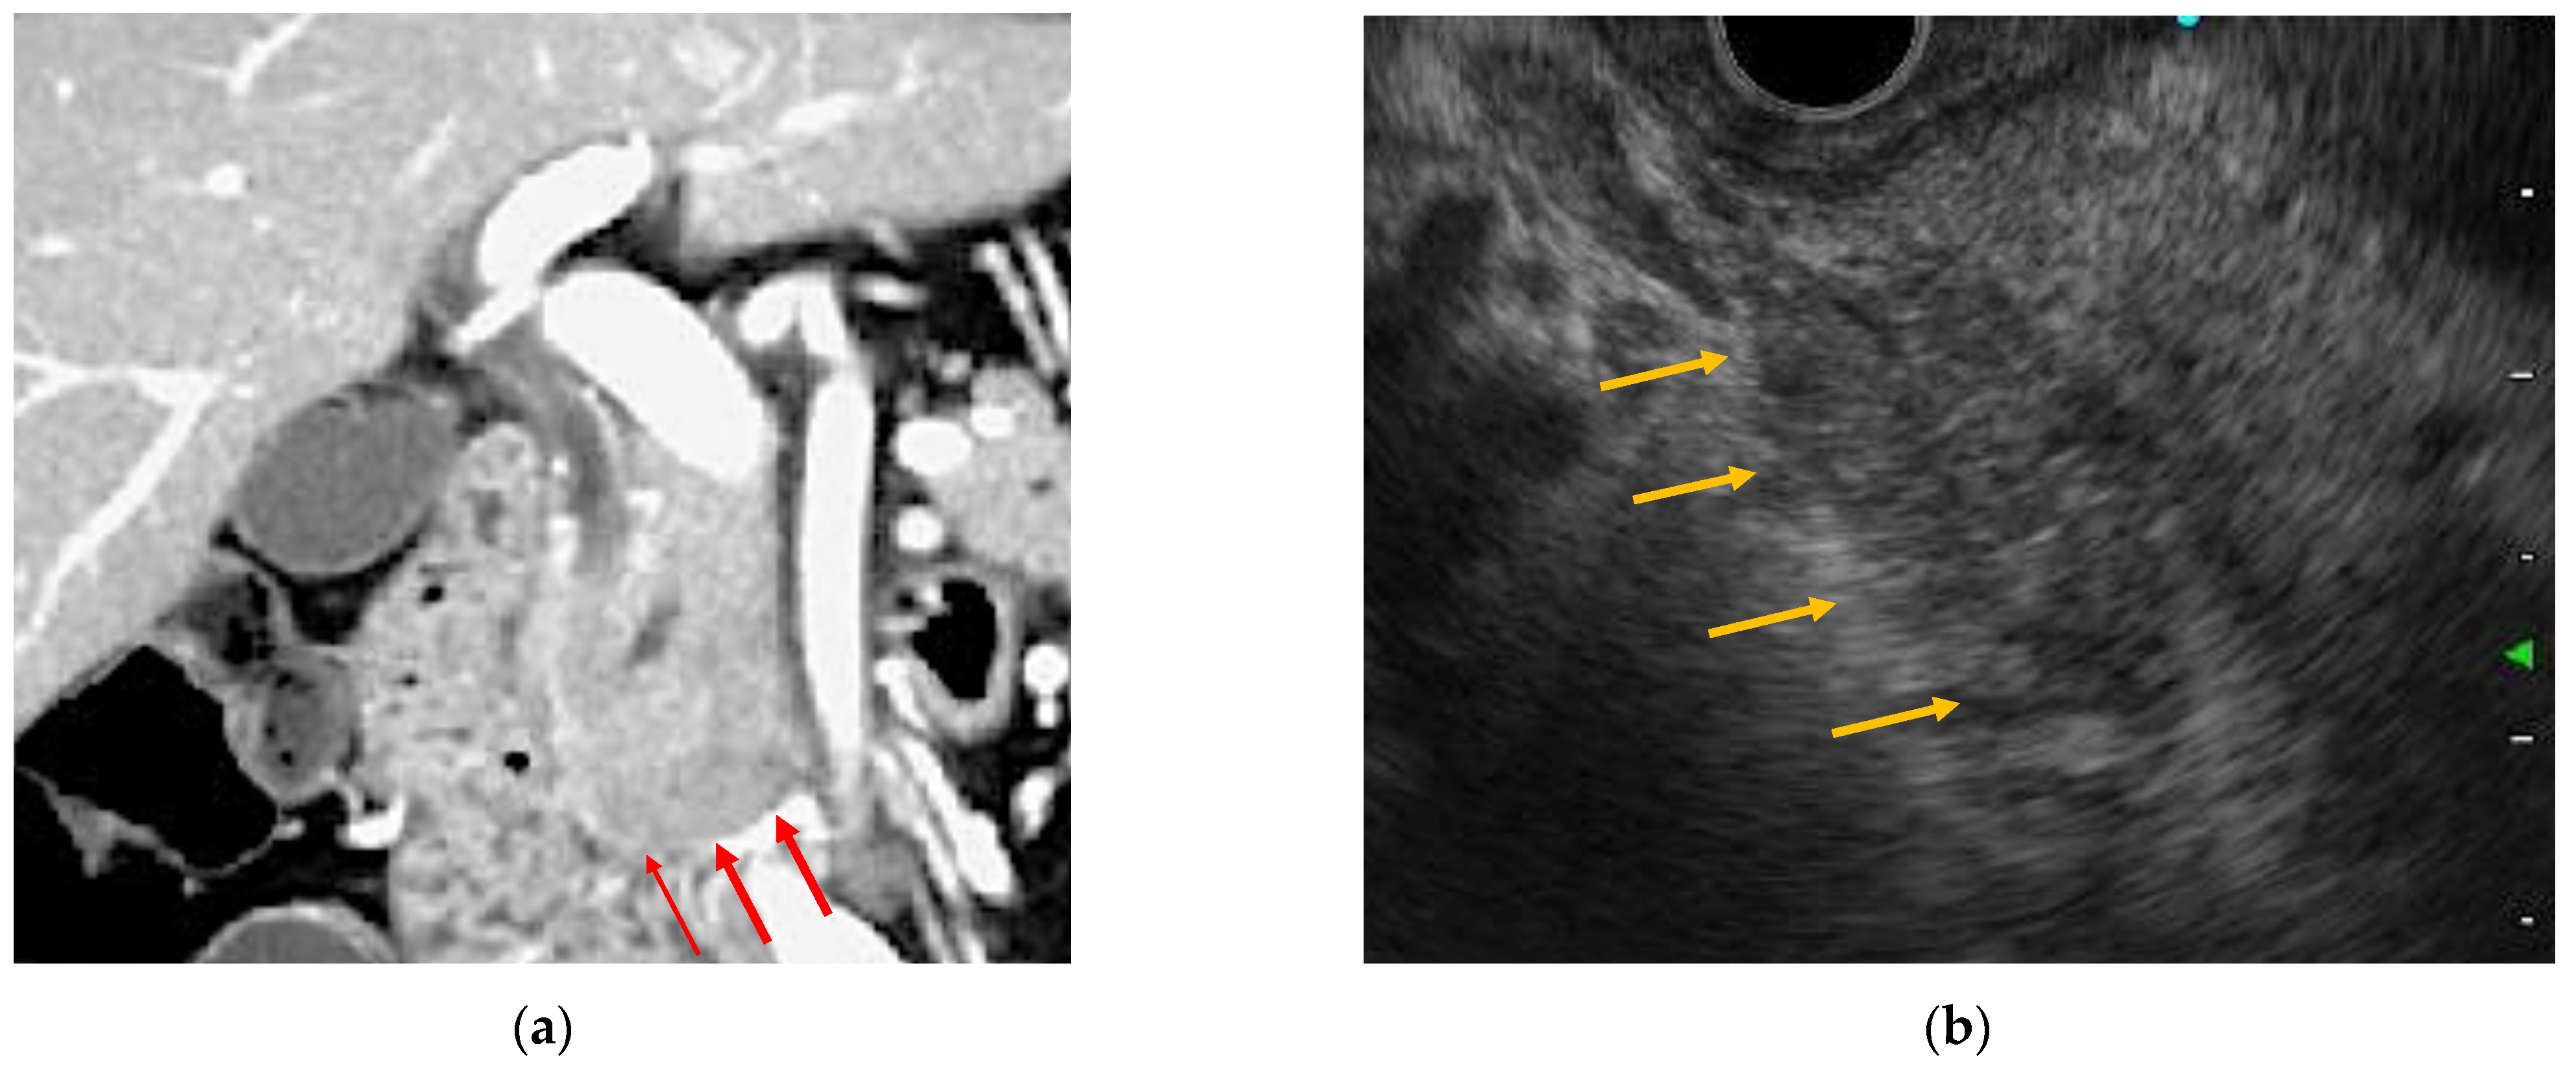

2.2.3. Radiology Images

2.3.1. EUS